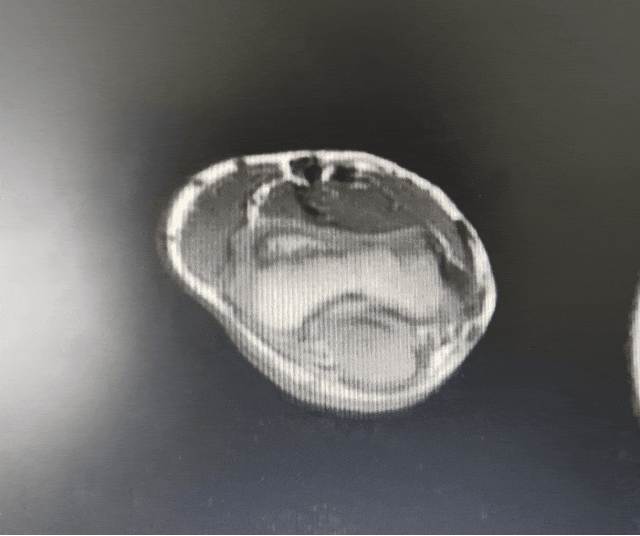

患儿家属7年前发现其右肘下方有一包块突起,并随着年龄逐渐增大,近半年出现活动时包块处疼痛不适,门诊以“右上肢血管畸形”收住我科。随后我科完善检查病例讨论,制定治疗方案,与家属沟通取得同意后,邀请西交大二附院小儿外科郭新奎教授、皮肤科谭宣丰教授共同协作进行皮肤及皮下血管瘤切除术手术治疗,手术过程顺利,患儿术后状况良好。